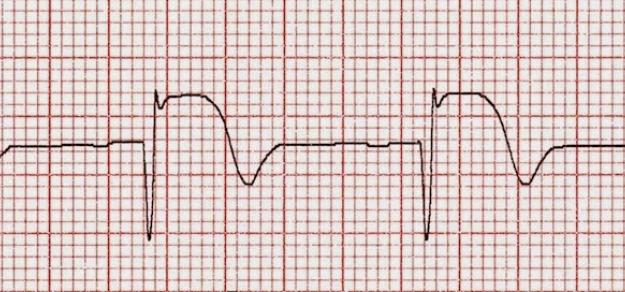

Pacientes con infarto agudo derivados a centros de hemodinamia en Argentina

19 septiembre 2017

Uno de cada tres pacientes es derivado para reperfusión miocárdica, pero los derivados tienen menor probabilidad de recibir tratamiento de reperfusión y menor utilización de angioplastia primaria. Una mejor articulación de las redes podría mejorar el acceso y disminuir la morbimortalidad. Revista Argentina de Cardiología, 2017 Nº 2